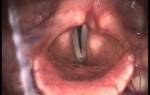

Если заболевание не лечить, оно может привести к острым стенозам гортани. Для диагностики применяются мазок из зева и ларингоскопия:

- При остром течении наблюдаются гиперемия слизистой гортани и голосовых связок, а также наличие слизи; в случае гриппа могут выявляться кровоизлияния в слизистую.

- При хроническом ларингите отмечаются застойный отек, гиперемия, небольшое утолщение слизистой, а в просвете гортани можно увидеть густую слизь.